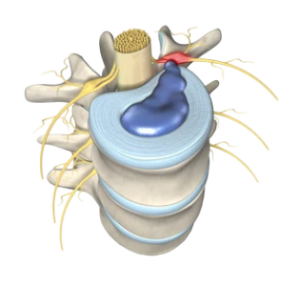

Η άσκηση με EMS βοηθά στην ενεργοποίηση βαθιών σταθεροποιητικών μυών που υποστηρίζουν τη σπονδυλική στήλη και τις αρθρώσεις.

Η βελτίωση της μυϊκής λειτουργίας συχνά συμβάλλει στη μείωση της επιβάρυνσης που δέχονται οι αρθρώσεις.

Κοιλιακοί Προσαγωγοί Σκολίωση Κύφωση